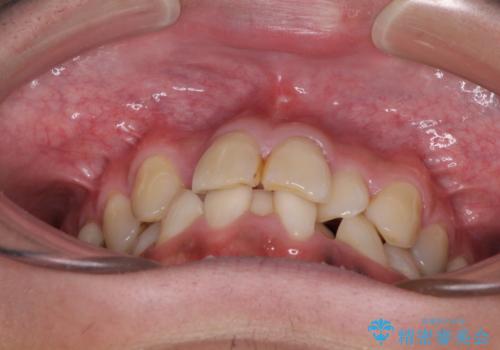

重なって磨きにくい上下の前歯 ワイヤー装置での抜歯矯正

- 前歯のデコボコを改善したいと来院された患者様です。

口元の突出感はないものの、上顎前歯のデコボコが著しかったため、上下顎左右小臼歯4本を抜歯することとしました。

上下の正中位置を改善するため、右下は第一小臼歯を、その他は第二小臼歯を抜歯することとしました。